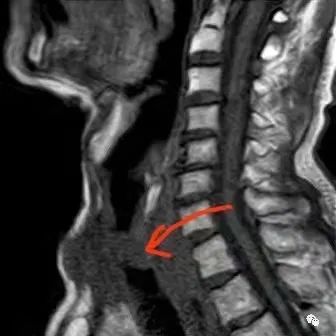

「胸科速度」半小時完成氣管支架置入術(shù) 成就患者過團(tuán)圓年原來,今年74歲的謝大爺在甲狀腺癌術(shù)后4個月出現(xiàn)咳嗽氣逼3天,行胸部CT檢查發(fā)現(xiàn)聲門下氣管腫瘤侵犯,致氣管嚴(yán)重狹窄。家屬聽聞我院陳中書博士團(tuán)隊(duì)在這個領(lǐng)域享有盛譽(yù),1月29日14時,通過當(dāng)?shù)蒯t(yī)院聯(lián)系上陳中書,咨詢能否救治該患者,并傳來患者的病情介紹。看到患者的影像學(xué)資料后,陳中書表示:“患者情況危急,隨時有窒息死亡的風(fēng)險(xiǎn),需要盡快解除大氣道梗阻,不管什么時間到醫(yī)院,我們都會盡自己所能,搶救患者。”

此時內(nèi)鏡介入室的麻醉和護(hù)理團(tuán)隊(duì)已全部準(zhǔn)備到位,陳中書和施天生醫(yī)生通過鼻腔快、準(zhǔn)、穩(wěn)地將導(dǎo)絲送入謝大爺?shù)臍夤埽殡S著謝大爺一聲刺激性咳嗽聲,支架成功置入氣管。監(jiān)護(hù)儀上謝大爺?shù)难躏柡投然謴?fù)至97%,呼吸恢復(fù)了平順,在場的醫(yī)護(hù)人員也都跟著松了一口氣,手術(shù)一切順利,時長僅半個小時。

「胸科速度」半小時完成氣管支架置入術(shù) 成就患者過團(tuán)圓年 氣管支架置入術(shù)后患者轉(zhuǎn)危為安。1月30日正是除夕前一天,患者情況良好,開心地辦理了出院,正好趕上回家過個團(tuán)圓年。